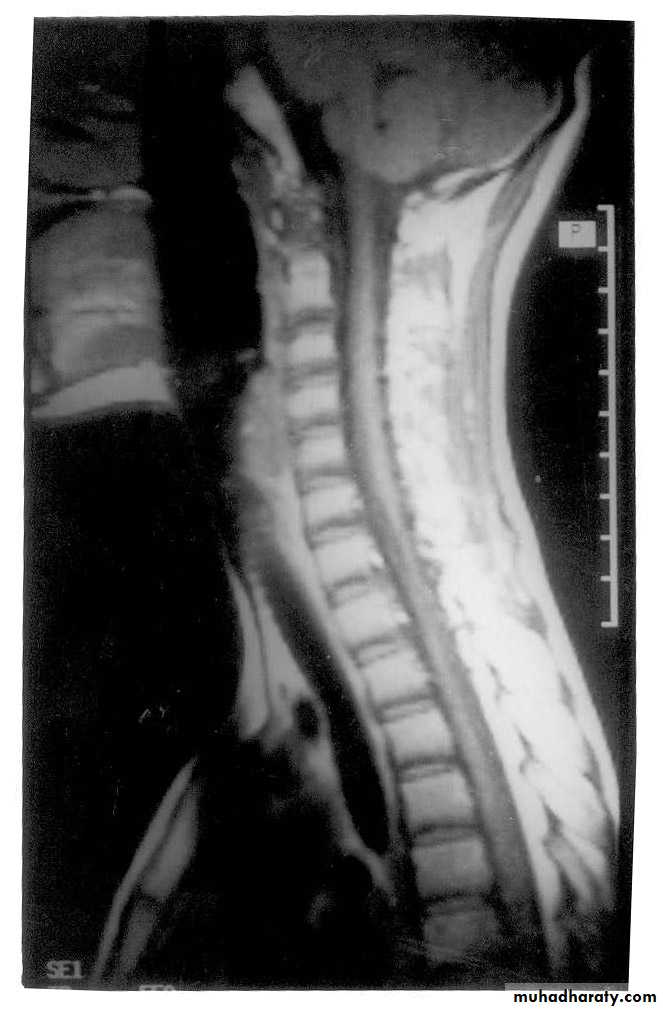

General examinations

ImagingPlain x-rays

Computed tomography (with mylography)

MR imaging

INFECTIONS OF BONE

Tuberculosis of the thoracic or lumbar spinePyogenic infection of the thoracic or lumbar spine